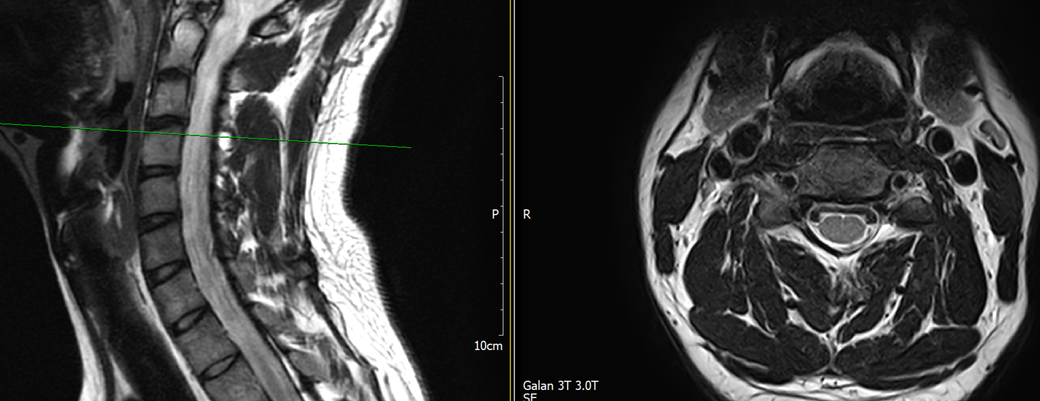

목과 오른쪽 어께 통증이 있어 mri를 찍어왔는데, 사진에서 의심되는 부분 있을까요?

• 3번 째 사진

MRI만 보면 굉장히 깨끗한 목입니다.

디스크탈출은 없고 신경뿌리가 압박될만한 모습도 전혀 보이지 않습니다.

지금은 MRI에서 잘 보이지 않는 디스크내장증일 가능성이 높아보이며 경추전만 자세를 잘 유지해주시는게 가장 큰 도움이 되겟습니다.